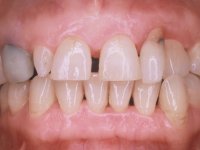

A paciente queixava-se que tinha um dente da frente a abanar, não gostava do “canino escuro” e também “queria fechar os espaços entre os dentes”. Passados 8 anos do tratamento inicial, o que motivou uma segunda fase de tratamento foi os “dois dentes da frente estarem feios”. Um ano após a última intervenção, apareceu um terceiro motivo para a terceira fase de tratamento, que foi a fratura da faceta feldspática colocada no dente 2.1.

Paciente do sexo feminino, com 47 anos não fumadora. Apresentou-se na consulta com o dente 1.3 com tratamento endodôntico e com um espigão falso coto fundido, reabilitado com uma coroa provisória. Os dois incisivos laterais superiores são conoides e de reduzida dimensão. O dente 2.2 apresenta mobilidade, consentânea com uma significativa reabsorção óssea entre o dente 2.1 e o dente 2.3 Os dois incisivos centrais estão separados por um diastema de 3mm e o dente 2.3 apresenta uma oclusão cruzada com o dente antagonista. Verifica-se também a ausência de alguns dentes posteriores e uma higiene oral razoável. Na segunda intervenção realizada passados 8 anos, verificou-se que os incisivos centrais superiores se apresentavam cromaticamente mais escuros e apresentavam um sulco longitudinal no esmalte que estando pigmentado comprometia esteticamente o sorriso. O trabalho realizado na primeira fase do tratamento mostrava-se competente estética e funcionalmente. Por fim, um ano após a última intervenção, a paciente apresentou-se com uma fratura da faceta colocada no dente 2.1 provavelmente em resultado de estar em contacto com o coto do implante. A rigidez da anquilose implantar, pode ter sido a causa desta fratura. Outros casos deste tipo de fratura já foram observados por mim em situações clínicas idênticas. A faceta do dente 1.2 apresentava-se esteticamente comprometida e a própria estrutura dentária apresentava uma pequena cárie e, pelo que se recomendaria a sua substituição.

Oito anos depois, na segunda intervenção, foi proposto o seguinte tratamento:

• Reabitação dos dentes Incisivos Centrais Superiores com facetas de cerâmica feldspática.

O tratamento iniciou-se com a re -preparação do coto do espigão falso coto fundido, com o objetivo de colocar as linhas de acabamento cervical com uma localização intra-sulcular e simultaneamente confecionar uma coroa provisória adaptada. Com um tratamento ortodôntico muito simples, fechou-se o diastema entre os incisivos centrais superiores e estabilizou-se esta posição com um arame colocado na superfície palatina dos centrais, funcionando como contenção. Posteriormente procurou-se fazer uma tração ortodôntica lenta do dente 2.2 com o intuito de diminuir, ainda que muito ligeiramente a perda óssea vertical nessa zona. Finalizada a tração, foi feita a extração do dente 2.2 e a zona foi reabilitada provisoriamente com uma coroa de resina composta colada aos dentes adjacentes. Foi colocado um implante dentário na zona do dente 2.2 sendo novamente colada a coroa provisória em resina, reabilitando provisoriamente a paciente durante o período de osseointegração. No dente 1.3 foi feita uma gengivectomia com bisturi elétrico, com a intenção de subir o nível cervical do 1.3 conseguindo uma maior harmonia com o dente 2.3. Estabilizados os tecidos moles, foi feita uma impressão com a técnica de moldeira aberta, utilizando silicones de adição de consistência “putty” e “light”. A recolha da cor, tanto da componente dentária como dos tecidos moles foi feita pelo ceramista no consultório.  No laboratório as impressões foram passadas a gesso e deram origem a modelos de trabalho que foram devidamente analisados. Foi decidido confecionar um “abutment” metalo-cerâmico aparafusado sobre o implante. Este “abutment” foi fundido com uma liga nobre e posteriormente revestido a cerâmica coronária e gengival. Dada a inclinação do implante o aparafusamento condicionou de forma inevitável a saída do orifício do parafuso pela superfície vestibular. No sentido de esconder esta situação, o desenho do “abutment” já foi idealizado com a intenção de acomodar na superfície vestibular a colagem de uma faceta feldspática. Este “abutment” foi provado em boca e foram feitos ajustes no componente cerâmico gengival. A sua adaptação aos tecidos moles foi feita tanto de forma subtrativa, com broca, como de forma aditiva, acrescentando resina composta de tonalidade gengival. Este acrescento de resina seria orientador do ceramista na colocação final da cerâmica de tonalidade gengival. A coroa que reabilitaria o dente 1.3 foi cimentada nesta consulta de prova com cimento de ionómero de vidro reforçado com resina composta. Finalizado o trabalho em laboratório da faceta sobre o 1.2 e o “abutment” e a faceta para o implante este foi colado em boca, após a colocação do isolamento absoluto. O trabalho satisfez plenamente a paciente. Durante oito anos a paciente foi seguida regularmente, mostrando-se agradada com o tratamento efetuado, no entanto começou a mostrar interesse em intervir esteticamente nos incisivos centrais superiores. Decidida a segunda fase da nossa intervenção, foi feita a preparação dentária dos dentes 1.1 e 2.1 para a colocação de duas facetas feldspáticas. Particular cuidado foi tido na preparação inter-proximal distal junto ao “abutment” do implante. Foi preciso avaliar muito pormenorizadamente o eixo de inserção da faceta em relação ao “abutment”. As facetas feldspáticas foram confecionadas em laboratório e posteriormente coladas em boca após a colocação de isolamento absoluto. Um ano após, iniciamos a nossa terceira fase de tratamento, após a faceta colada no dente 2.1 ter fraturado. A preparação dentária foi feita sobre a faceta colada, procurando estender mais para palatino o interface inter-proximal distal. O objetivo seria passar para mais palatino do ponto de contacto o interface faceta-dente. O preparo dentário do dente 1.2 também foi muito reduzido, limitando-se a criar um eixo de inserção. Após confecionadas a coroa total e a faceta em laboratório foram coladas em boca. Primeiro foi colada a coroa utilizando-se um isolamento relativo com teflon, posteriormente foi colada a faceta após a colocação do isolamento absoluto. Na coroa utilizei este tipo de isolamento para evitar a utilização de grampos. Seria difícil de aplicar pela forma e dimensão do dente e agressivo para os tecidos moles. Após a colagem foi avaliada a integração oclusal do trabalho.